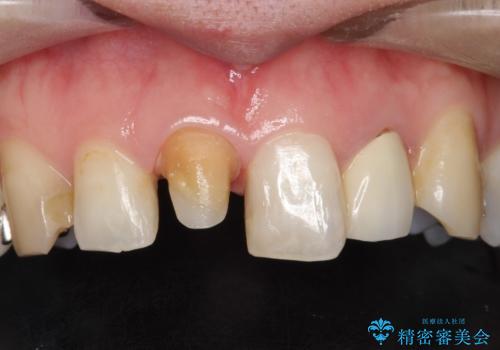

- 他院で装着された保険の前歯のかぶせ物が、他と歯と馴染まないので、自然な歯にしたいとのことで来院されました。

右上の1番目の歯の保険のかぶせ物と金属の土台を、ファイバーコアとオールセラミックにて再補綴する計画としました。